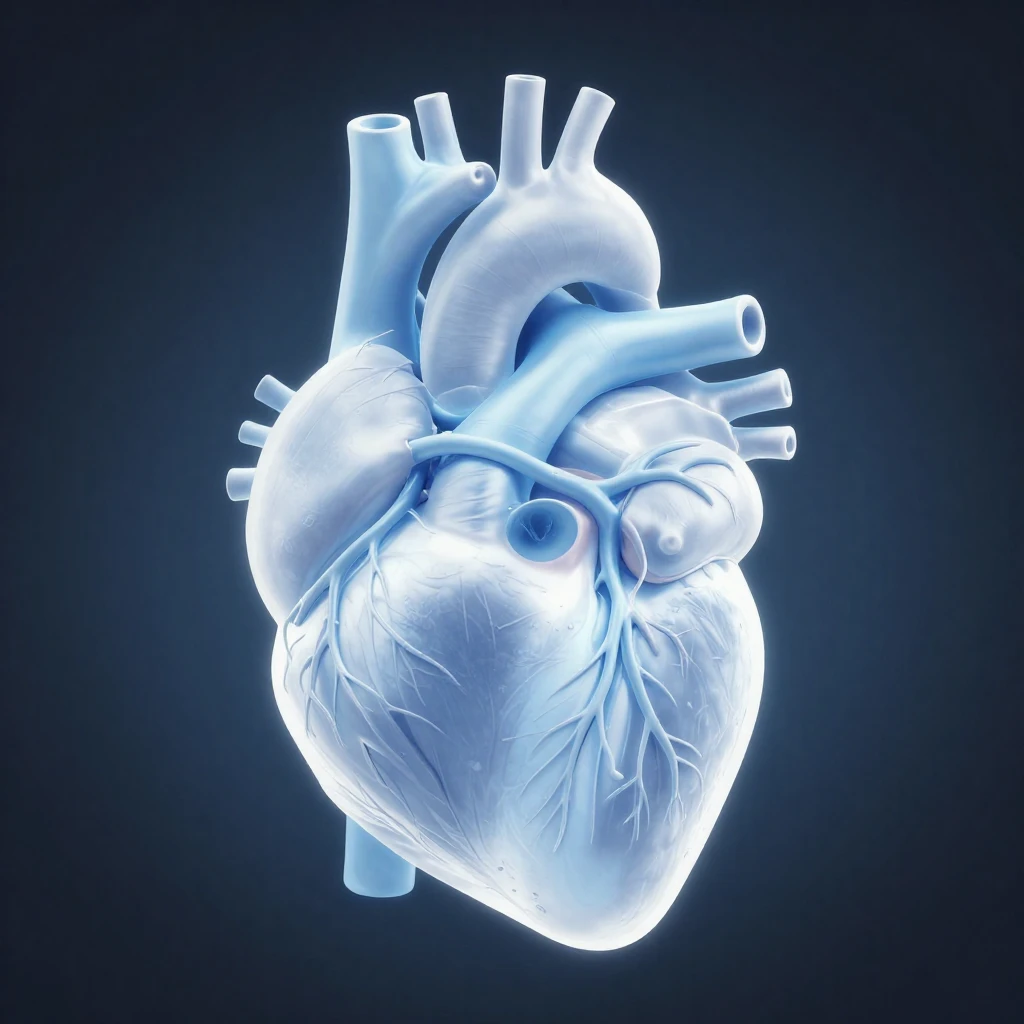

1024×1024

Quadrat 1:1

SD

Dieses Bild wurde von künstlicher Intelligenz erstellt. Es kann kostenlos heruntergeladen und überall verwendet werden – auf Websites, in Drucken, sozialen Medien oder kommerziellen Projekten.

Kostenlos

CC0

Gewerbliche Nutzung